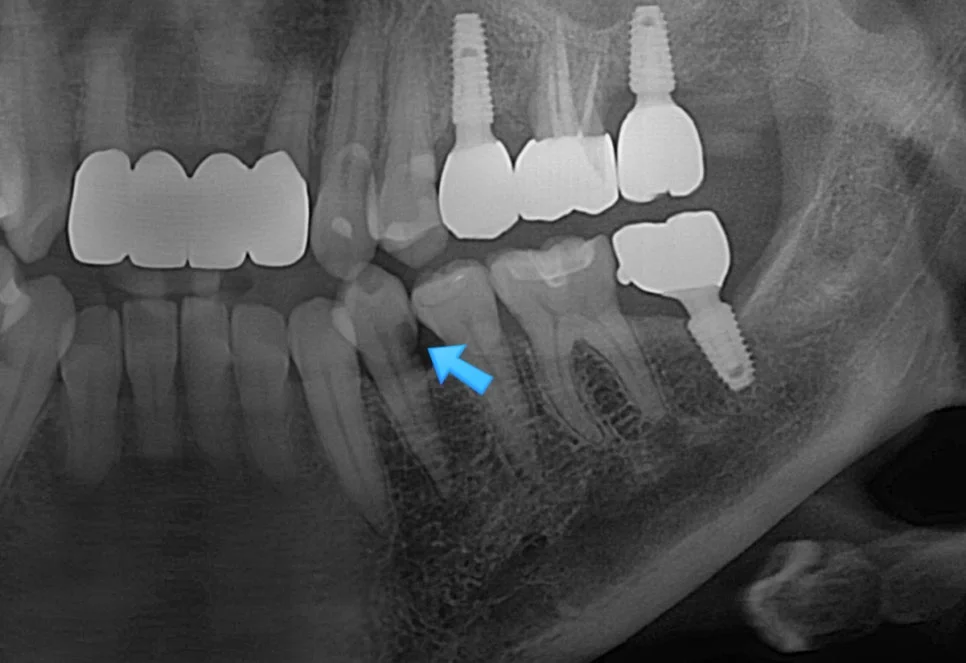

임플란트 틈새 진단 방사선 사진

X-ray에서 임플란트와 치아 사이 틈 확인

사진을 찍어보면 명확하게 임플란트와 치아 사이에 틈이 보이는데요. 이 정도 공간이면 음식물이 정말 엄청나게 끼게 됩니다ㅜ

음식물이 끼는 사이 틈에는 충치/잇몸질환이 둘 다 잘 생기게 되므로 음식물 끼임은 그 자체로 문제입니다ㅜ

긴밀해진 사이 틈 — X-ray로 확인

긴밀해진 사이 틈을 육안으로도 X-ray로도 확인할 수 있고, 주변 잇몸도 예쁘게 아문 것을 확인할 수 있습니다^^